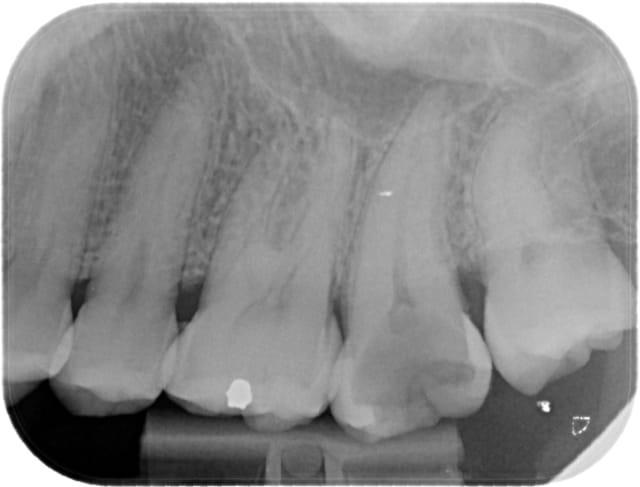

Un autre cas plus sympa, toujours au Wave One primary.

Ca marche super bien, par contre comme je pensais un peu ça ne fait pas gagner un temps inoui... si sur une endo d'une heure vous passez 5 minutes sur la rotation continue en elle même, vous en passerez peut être 1'30 (totalement pifométrique) sur le wave one, ce n'est pas ça qui va changer énormément la durée du rendez vous.

Waveone17 pr  q2fxwb - Eugenol

Waveone17post fcxjf1 - Eugenol

Et l'endo est très belle, bravo.